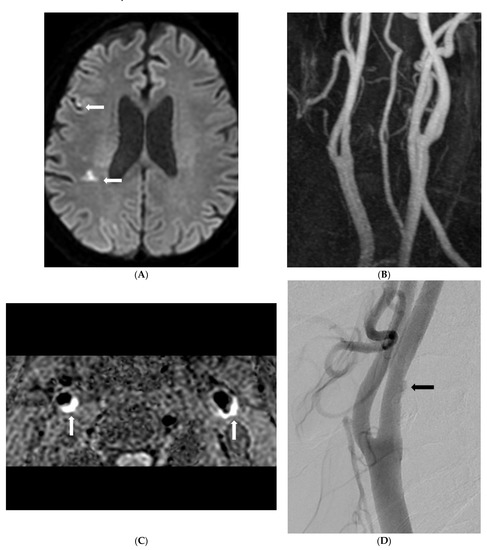

Morphological analysis of carotid plaques on SNAP imaging between the two groups is shown in Table 2. The presence of carotid IPH in the SyNC group was significantly higher than that in the non-SyNC group (88.2% vs. 50.0, p = 0.009). Carotid stenosis and maximal wall thickness of carotid plaques were significantly higher in the SyNC group (Figure 2).

Figure 2.

An 80-year old man with recurrent embolic stroke and symptomatic nonstenotic carotid disease. (A) Diffusion-weighted imaging shows diffusion restriction in right parietal white matter (arrows). (B) Carotid MR angiography shows mild stenosis of right proximal internal carotid artery. (C) SNAP imaging shows bilateral carotid intraplaque hemorrhage (arrows) and <50% carotid stenosis. (D) Carotid angiography shows focal ulceration of right carotid plaque (arrow). (E) Diffusion-weighted imaging shows multifocal and extended embolic infarction of right middle cerebral artery territory after one year. (F) Carotid angiography after recurrent embolic infarction showed increased ulceration and no interval change of stenosis (arrow).

Multivariate analysis was performed on factors associated with SyNC and ESUS (Table 3). Presence of carotid IPH (OR, 0.081 [0.01–0.672]; p = 0.02) and maximal wall thickness of carotid plaque (OR, 0.183 [0.034–0.978]; p = 0.047) were significantly associated with SyNC and ESUS.